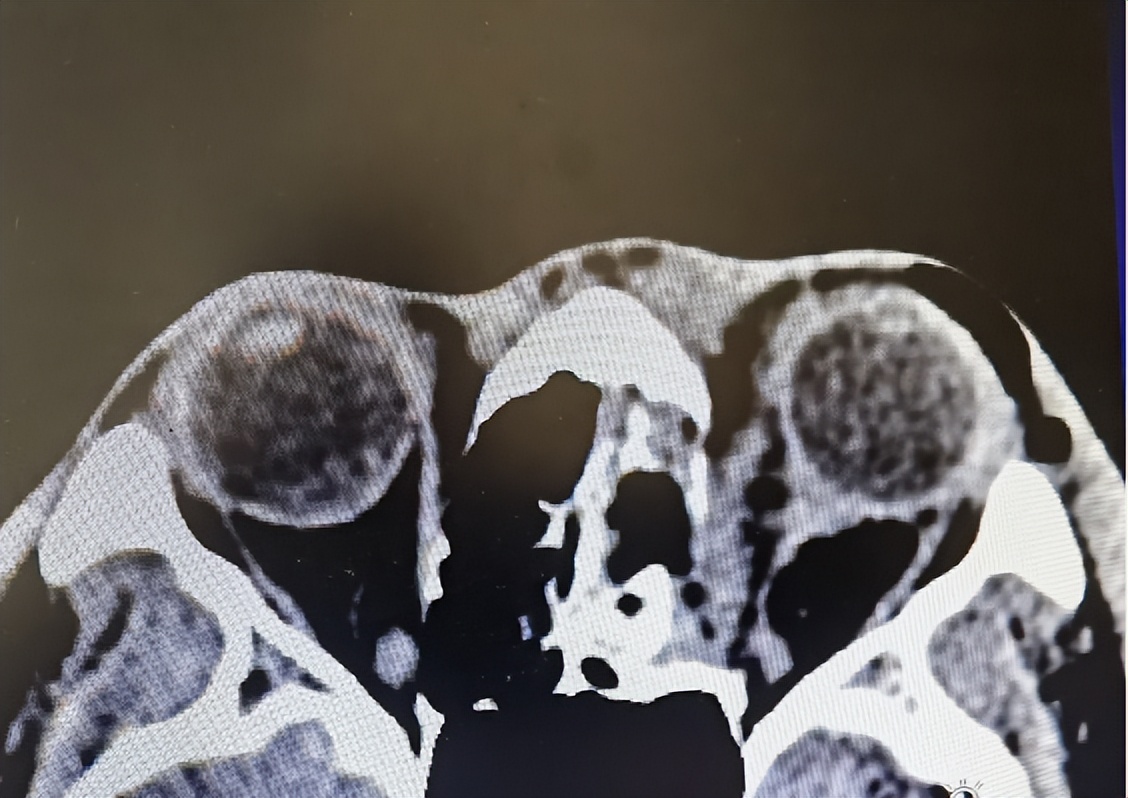

张某眼球明显内陷

救护车赶到后第一时间将他送到我院急诊。接诊的急诊外科主治医师谢杰马上对张某进行检查。检查发现,虽然伤情在外观上看着并不重,但张某左眼已经完全失明,左眼眼眶骨折,眼球凹陷明显,并且内陷达到1厘米,整个眼球的一半已经嵌到鼻腔里面。

伤情严重,谢杰马上呼叫眼科会诊,眼科值班医生张春明马上赶来,对张某进行进一步检查。尽管从CT影像上张某眼球外形完整,但受到外力撞击,眼球破裂的可能性不小,视神经也可能受到损伤。并且这些伤情都必须在手术中才能得到明确,后续治疗也才能明确和跟进。并且张某的伤情严重,根本拖不起,耽搁得越久,视力恢复的希望就越渺茫。

为了减少张某颜面部的损伤,不影响面容,手术团队通过鼻内镜,从张某鼻孔进入进行手术。手术中,医生们发现,张某受到撞击的眼球和周围的肌肉和脂肪组织已经内陷到鼻腔3厘米,鼻腔三分之二的空间都被占。但让医生们高兴的是张某的眼球竟然没破,视神经的损伤也不大,视力恢复的可能性不小。